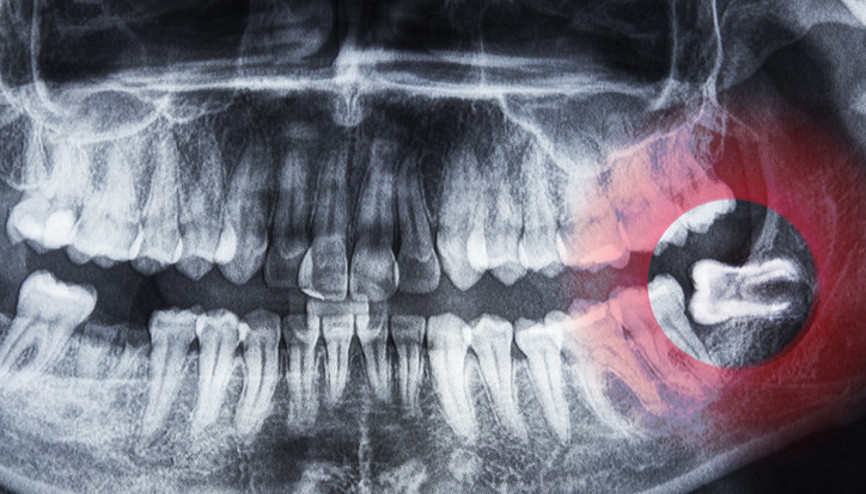

#SağlıkAğzınızın en arka bölgesinde zaman zaman hissedilen bir ağrı, çiğneme sırasında zorlanma ya da diş etinizde tekrarlayan şişlikler... Sebebi gömülü kalmış bir yirmi yaş dişi olabilir. Ağız, Diş ve Çene Cerrahisi Uzmanı Diş Hekimi Dr. Serap Özdamar, gömülü yirmi yaş dişlerinin nedenlerini, ne zaman çekilmesi gerektiğini ve operasyon süreciyle ilgili merak edilenleri anlattı.